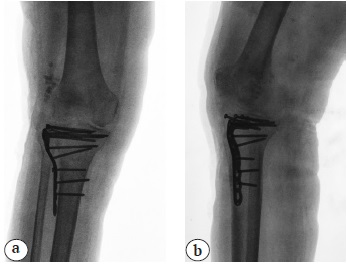

Через 2 нед. после выписки из стационара пациентка вновь поступила в отделение по экстренным показаниям с рецидивом лихорадки и местных признаков воспаления. Выполнены ревизия и дебридмент раны, постановка VAC-системы. Пациентка получала антибактериальную терапию с учетом результатов первичного посева: Цефтриаксон 1,0 г 2 раза в день. На фоне гипохромной анемии с уровнем гемоглобина 76 г/л проведена эффективная гемотрансфузия эритроцитарной взвеси, в результате чего уровень гемоглобина повысился до 96 г/л. На 5-е сут. выполнены повторная ревизия и дебридмент раны с заполнением подкожных дефектов мягких тканей цементными спейсерами с клиндамицином и гентамицином в виде бус, после чего рана ушита, конечность иммобилизирована гипсовой повязкой (рис. 5). Антибактериальная терапия продолжена левофлоксацином перорально 500 мг 2 раза в день. Рана зажила. На 11-й день после операции пациентка выписана на амбулаторное лечение с рекомендациями продолжения антибактериальной терапии до 8 нед. и гипсовой иммобилизации до 4 мес.

Рис. 5. Рентгенограммы после проведения операции повторного дебридмента раны с заполнением дефекта мягких тканей цементным спейсером с антибиотиками: a — прямая проекция; b — боковая проекция

Fig. 5. X-rays after redebridement of the wound with insertion of an antibiotic-impregnated cement spacer into the soft tissue defect: a — AP view; b — lateral view